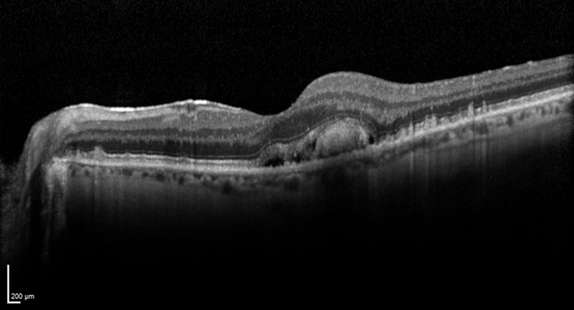

In neovascular AMD, also called WET AMD, abnormal blood vessels grow underneath the retina. These vessels can leak fluid and blood, which may lead to swelling and damage of the macula. The damage may be rapid and severe, unlike the more gradual course of Dry AMD. It is possible to have both DRY and WET AMD in the same eye, and either condition can appear first.

With neovascular AMD, abnormally high levels of vascular endothelial growth factor (VEGF) are secreted in your eyes. VEGF is a protein that promotes the growth of new abnormal blood vessels. Anti-VEGF injection therapy blocks this growth. If you get this treatment, you may need multiple monthly injections. Before each injection, your eye will be numbed and cleaned with antiseptics.

This technique involves laser treatment of select areas of the retina. First, a drug called verteporfin will be injected into a vein in your arm. The drug travels through the blood vessels in your body, and is absorbed by new, growing blood vessels. Your eye care professional then shines a laser beam into your eye to activate the drug in the new abnormal blood vessels, while sparing normal ones. Once activated, the drug closes off the new blood vessels, slows their growth, and slows the rate of vision loss. This procedure is less common than anti-VEGF injections, and is often used in combination with them for specific types of neovascular AMD.